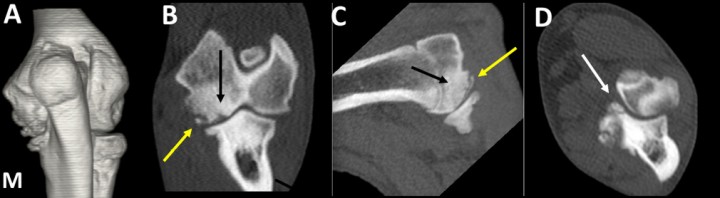

<p>Labrador Retriever macho de 5 meses, con cojera unilateral intermitente del codo izquierdo. Imagen en 3D del codo, en vista caudal (<strong>A</strong>) y planos dorsal (<strong>B</strong>), sagital (<strong>C</strong>) y transversal (<strong>D</strong>). Osteocondrosis del cóndilo humeral, con abundante hueso esclerótico (flechas negras) y un fragmento osteocondral desprendido del cóndilo (flecha amarilla). Se señala la fragmentación de la apófisis coronoides medial del cúbito (flecha blanca). Existe artrosis avanzada, especialmente manifiesta en la cara medial del codo (M).</p>

Labrador Retriever macho de 5 meses, con cojera unilateral intermitente del codo izquierdo. Imagen en 3D del codo, en vista caudal (A) y planos dorsal (B), sagital (C) y transversal (D). Osteocondrosis del cóndilo humeral, con abundante hueso esclerótico (flechas negras) y un fragmento osteocondral desprendido del cóndilo (flecha amarilla). Se señala la fragmentación de la apófisis coronoides medial del cúbito (flecha blanca). Existe artrosis avanzada, especialmente manifiesta en la cara medial del codo (M).

En 6 codos (9,1%) se detectó lesión en el cóndilo humeral (OCD o kissing lesion), todos concomitantes con EACM. La OCD consiste en un defecto en la osificación endocondral cuya lesión tiende a manifestarse en la superficie de carga de la zona medial del cóndilo humeral.[ Hornof W, Wind A, Wallack S, Schulz K. Canine elbow dysplasia: the early radiographic detection of fragmentation of the coronoid process. Vet Clin North Am Small Anim Pract 2000; 30: 257-266. [PubMed] ] La TC permite igualmente observar el defecto de osificación con o sin presencia de un fragmento cartilaginoso (flap). En la TC se aprecia una zona hipoatenuante en la parte medial del húmero, que puede ir acompañado de una reacción esclerótica.[ Reichle J, Park R, Bahr A. Computed tomographic findings of dogs with cubital joint lameness. Vet Radiol Ultras 2000; 41: 125-130. [PubMed] , Cook C, Cook J. Diagnostic imaging of canine elbow dysplasia: a review. Vet Surg 2009; 38: 144-153. [PubMed] ] Con la TC el mejor plano para evaluar la OCD es el dorsal, siendo también válido el sagital.[ Reichle J, Park R, Bahr A. Computed tomographic findings of dogs with cubital joint lameness. Vet Radiol Ultras 2000; 41: 125-130. [PubMed] , Cook C, Cook J. Diagnostic imaging of canine elbow dysplasia: a review. Vet Surg 2009; 38: 144-153. [PubMed] ] Los fragmentos de la apófisis coronoides medial, especialmente si están desplazados, pueden erosionar el cóndilo humeral dando lugar a lesiones por roce o contacto (kissing lesions).[ Groth A, Beningni L, Moores A, Lamb C. Spectrum of computed tomographic findings in 58 canine elbows with fragmentation of the medial coronoid process. J Small Anim Pract 2009; 50: 15-22. [PubMed] ] En ocasiones resulta difícil diferenciar estas lesiones de las producidas por la OCD.[ Chico A. Overview of elbow dysplasia screening in Spain. Proc 32th Ann Meet Int Elbow Working Group. Barcelona (Spain): 2018: 12. , Hornof W, Wind A, Wallack S, Schulz K. Canine elbow dysplasia: the early radiographic detection of fragmentation of the coronoid process. Vet Clin North Am Small Anim Pract 2000; 30: 257-266. [PubMed] ]